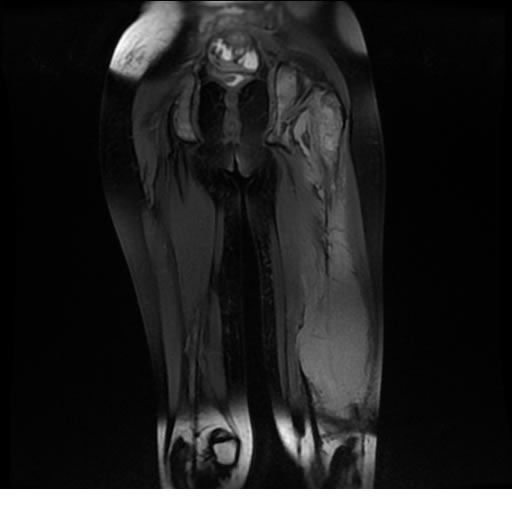

Se realiza estudio de MRI de muslo izquierdo en diferentes planos, con secuencias de Spin Echo, GRE; ponderadas a T1 y a T2, se utilizan pulsos de saturación de grasa y se administra medio de contraste IV a base de Gadolinio en base al peso del paciente.

La diáfisis femoral izquierda muestra reacción perióstica importante, se extiende desde el cuello del fémur, invade trocánteres, diáfisis femoral, medial y distal, es compatible con un proceso infeccioso óseo, el complejo muscular del muslo se ve edematizado.

Hallazgos en Resonancia Magnética (RM)

La resonancia es la modalidad de elección para valorar la extensión intramedular y la infiltración en tejidos blandos, brindando una imagen más detallada del compromiso tumoral. Los hallazgos característicos incluyen:

Lesión de señal heterogénea en secuencias T1 (hipointensa) y T2/STIR (hiperintensa), que refleja necrosis, hemorragia y contenido celular diverso.

Realce intenso y heterogéneo tras la administración de contraste (gadolino), lo que indica vascularización tumoral.

Compromiso de la médula ósea adyacente y de estructuras vecinas, como músculos y neurovasculatura.

Posible presencia de edema óseo y necrosis central.